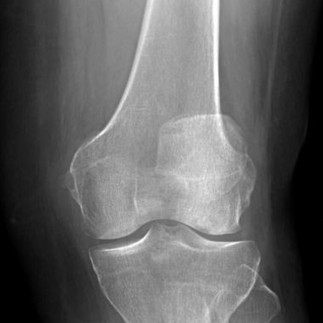

TRIGGER WARNING: Post-surgery image of knee

Betty had visited the doctors several times in the past 50 years and has only just been diagnosed this year. Here is a copy of her X-ray scans showing her shallow trochlear groove and dislocation of the patella:

Betty's x-ray scans showing her Trochlear dysplasia | Photos by Betty Holden